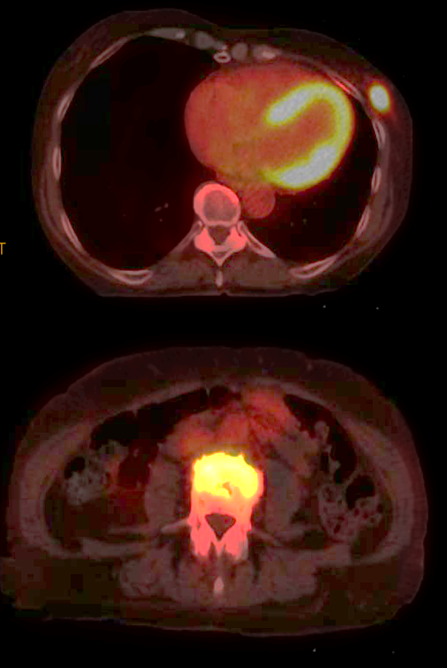

الحالة الأولى: تم اكتشاف كتلة في الثدي الأيسر. ثم تشخيصها بعد عمل خزعة بالأشعة التلفزيونية. تم عمل PET CT بعد ذلك واتضح وجود الكتلة وانتشار لأحد فقرات الظهر. ثم عمل ال MRI ويتضح وجود الكتلة في الجزء الخلفي الخارجي للثدي الأيسر.

تم علاج المريضة بعلاج اشعاعي لمنطقة الفقرة المصابة وعلاج السرطان بالعلاج الكيماوي واختفى بعد ذلك في الرنين المغناطيسي ثم تم استئصاله كاملا والحمدلله.